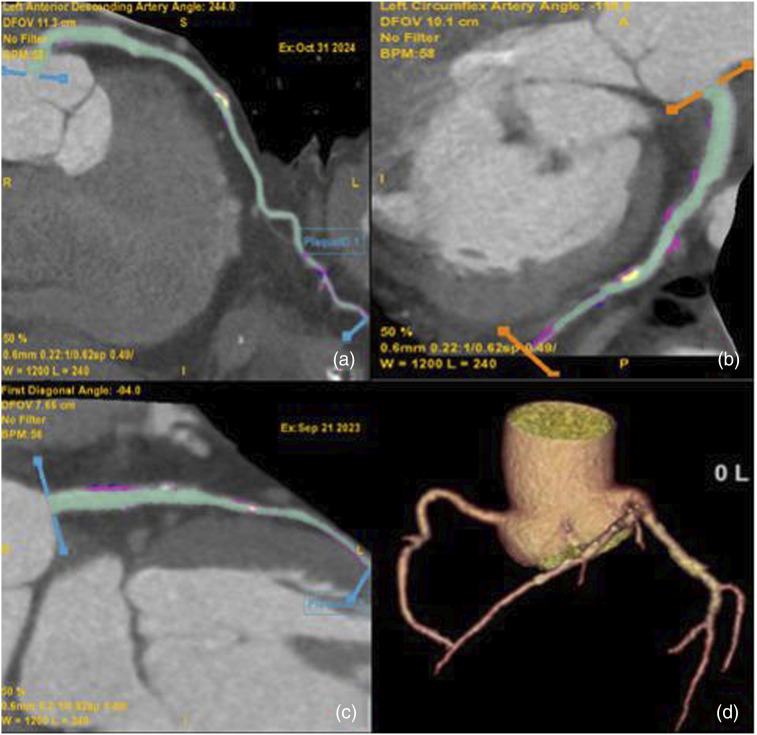

Material and methods: A Retrospective study including 103 patients (64M, 39F) who underwent coronary computed tomography was retrospectively examined at a single center. PCAT and high-risk plaques were measured independently and compared to stenosis and coronary artery type. Adipose tissue attenuation, ranging from -180 to -25 HU, was measured along the plaque's length and in a 0.5-1 mm region around the perilesional coronary arteries.

Results: The PCAT values increases with the degree of stenosis in the LAD, Cx, and RCA (r = 0.9161, p < .001; r = 0.9717, p < .001; r = 0.9315, p < .001, respectively). PCAT values demonstrate a positive pattern when plaque length increases in all coronary arteries (r = -0.6316, p < .001; r = -0.8825, p < .001; r = -0.7529, p < .001; LAD, Cx, RCA). PCAT values differed significantly based on plaque type in all coronary arteries. Calcified plaques showed statistically significant differences compared to both soft and mixed plaques (p < .05). Patients with positive remodeling had PCAT values of -69.43 (±8.76) HU, while cases without positive remodeling had PCAT values of -84.54 (±7.65) HU, indicating a significant difference (p < .05).

Abstract Image